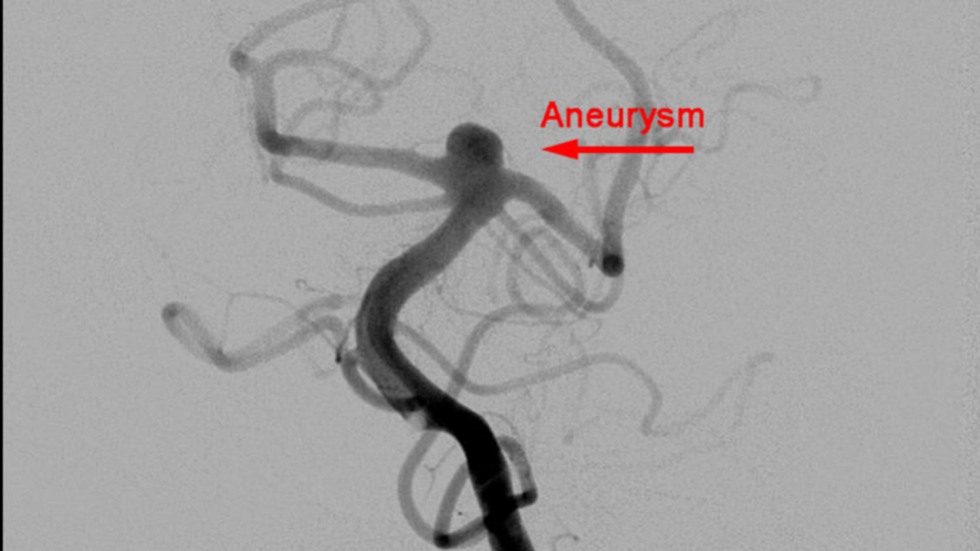

Primary Coil Embolization, Technique: Aneurysm

1 of 3

Primary Coil Embolization: Treats aneurysm from the inside rather than the outside. Fill aneurysm with embolic coils in order to obliterate blood flow.